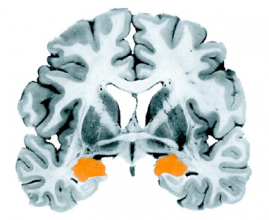

Amygdala

Above: The amygdala is outlined in orange on this photograph of a coronal section of a post-mortem human brain.